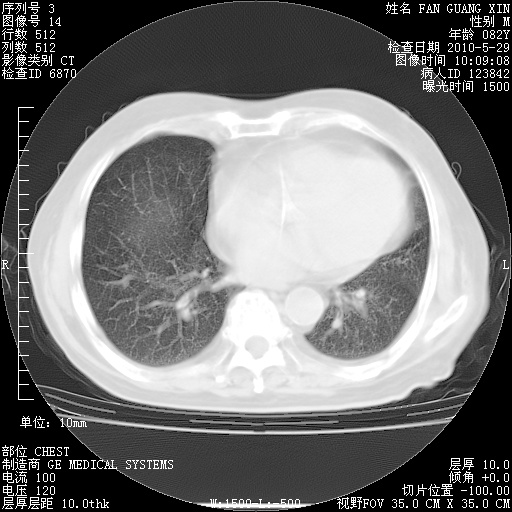

再治疗10天后的肺部CT

肺部体征:呼吸25次/分,心率100次/分,呼吸音增粗。无干湿罗音。

血常规:15.36×10 [sup]9[/sup]/L  N0.92  L0.036  M0.045 ESR 27mm/h。

血生化:白蛋白33.30g/L  球蛋白23.67g/L  CRP 32.82mg/L 肝肾功能正常。电解质正常。

从白细胞总数和中性比例看好像合并感染。肺部纹理好像比上次多,支气管炎?其他感染?

阅读此次胸部CT,肺间质渗出性改变较入院时有吸收。目前从体温、白细胞、中性分叶明显增高,肯定存在细菌感染(发生医院感染哦,若无消化道及泌尿系统等感染的依据,肺部感染可能大)。若你院头孢哌酮舒巴坦钠耐药率较高,同意你的方案,若48小时体温仍高,可考虑使用碳青霉稀类抗菌药物,同时可予超声雾化、注意滴数时加大液体量。白蛋白33.30g/L较低哦,需加强营养等支持治疗。